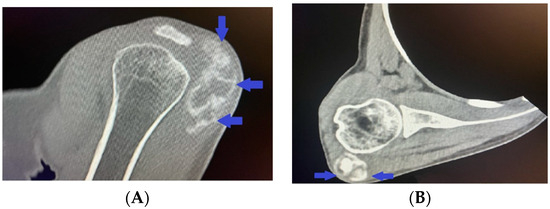

A hetero-dense cloud-like lesion measuring 5.22 × 1.87 cm with soft-tissue and calcium-equivalent densitometric density was seen in the right deltoid muscle at the level of the clavicle and lateral to the right humeral head, without involving neighboring bones and structures, according to spiral computed tomography with 3D reconstruction (Figure 3A,B).

Figure 3.

(A,B) Computed tomography with 3D reconstruction showing cloud-like lesion with soft-tissue and calcium-equivalent densitometric density in the right deltoid muscle lateral to the right humeral head and not involving adjacent bones and structures.